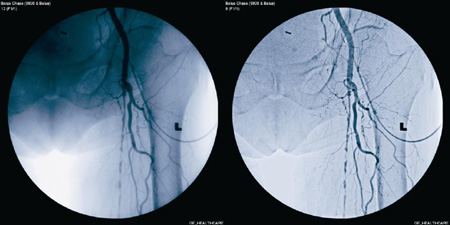

OEC 9900 Eliteの高画質を実現するのが,GE製据付型デジタル式循環器用X線透視診断装置Innova(イノーバ)シリーズにも採用され高い評価を獲得している画像処理技術「ダイナミックレンジマネージメント(DRM)」。 ステントグラフトをはじめとする高機能デバイスを使用した大動脈瘤や冠動脈プラークの手術など,血管内治療の高度化に伴い,患部やデバイスなどの一段と高い視認性が要求されている。従来視認性を向上するには,Windowingのような画像全体のコントラストの変換が主流であったが,画質が向上されるのが特定部位に限られるという問題があった。OEC 9900 Eliteでは,新画像処理技術「ダイナミックレンジマネージメント(DRM)」を搭載,骨や軟部組織,デバイスなど画像情報を構成する複数の空間周波数成分を的確に処理することで,血管ならびにデバイス両方の視認性向上を実現している。この最先端の画像処理技術によって,OEC 9900 Eliteは高度化するインターベンションにも対応可能な画像を描出する(図参照)。

従来機種(左)とOEC 9900 Elite(右)で撮影した血管造影画像GE独自のDRMにより、血管を明瞭に描出

従来機種(左)とOEC 9900 Elite(右)で撮影した血管造影画像

GE独自のDRMにより、血管を明瞭に描出